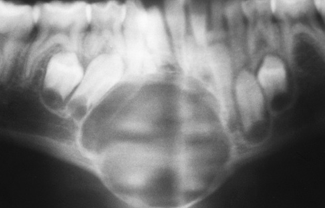

aneurysmal bone cyst